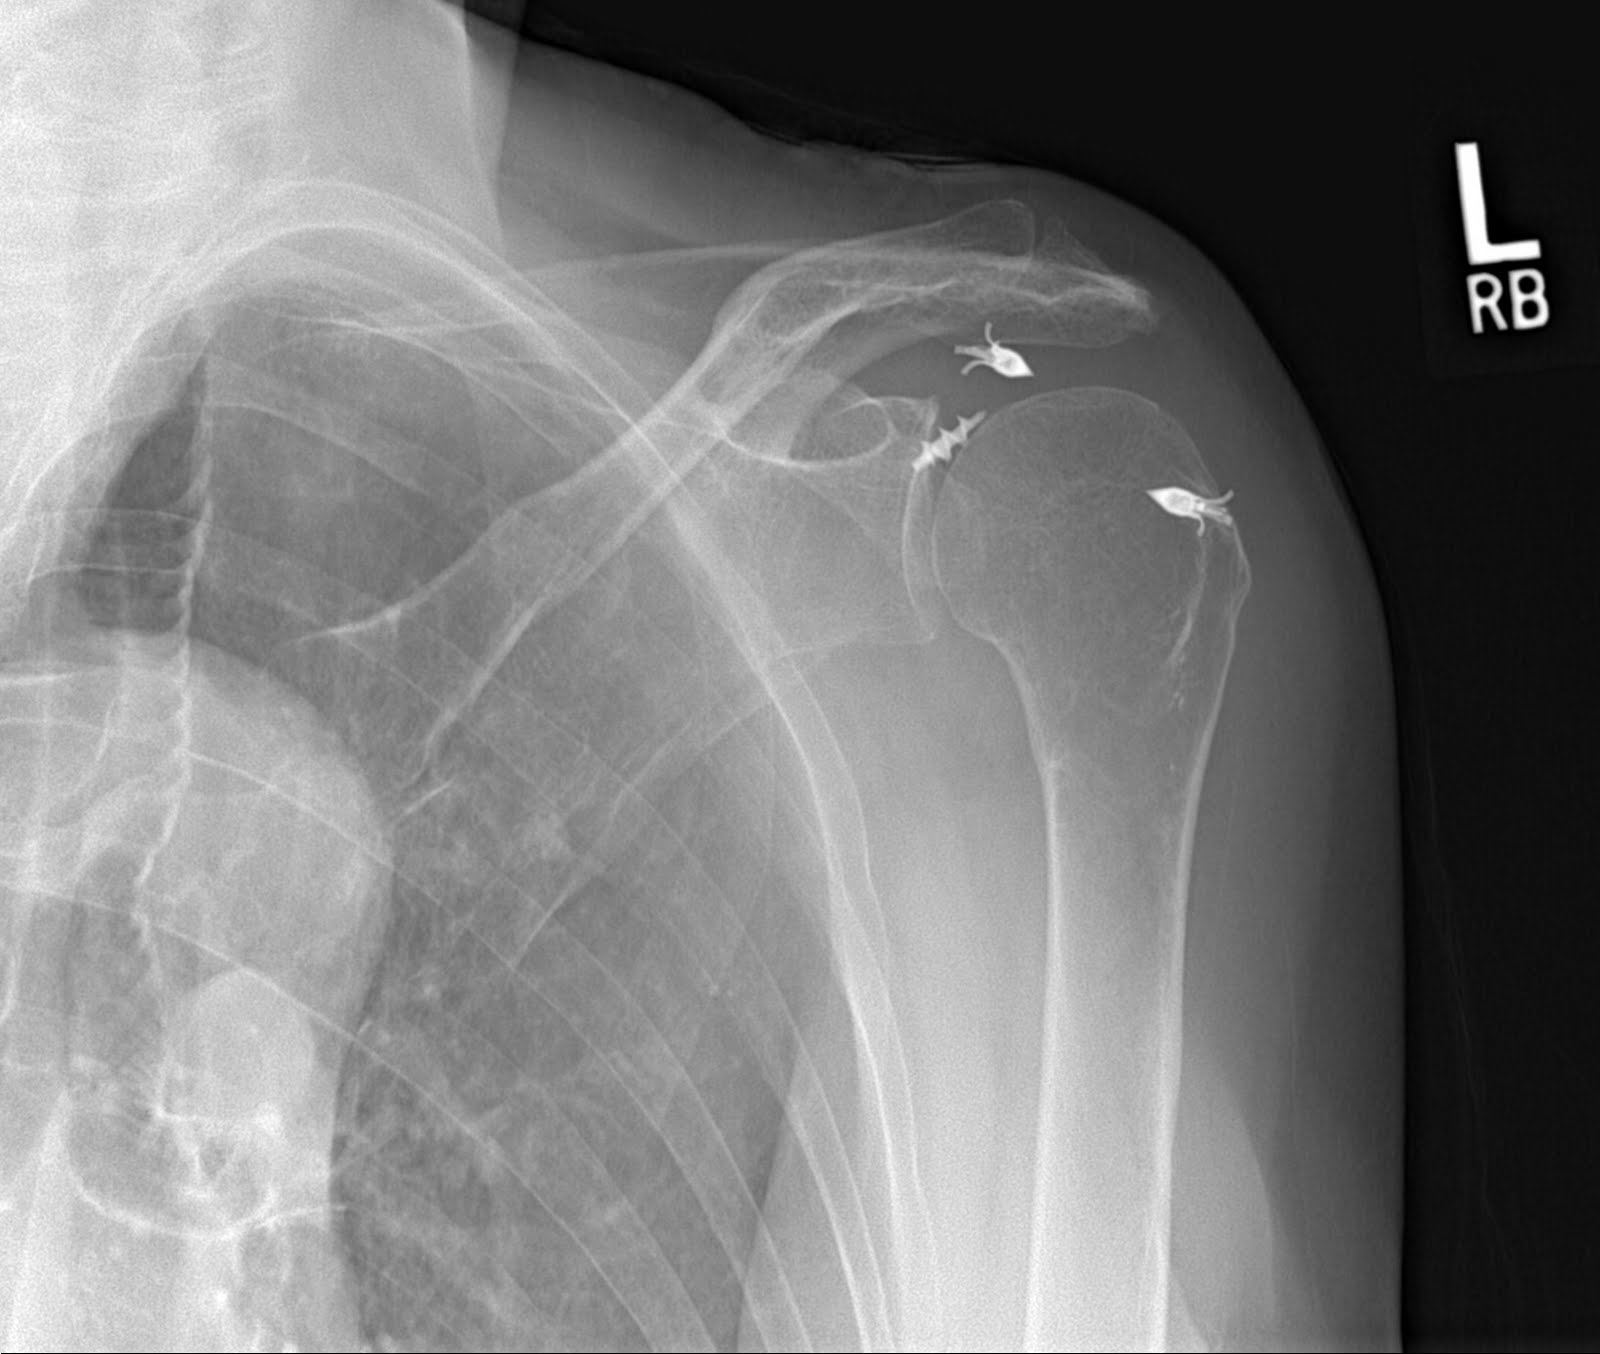

So one day in the office, an older patient comes in and says she had a left rotator cuff repair by Dr. Kishmeintookus (not his real name, of course) and she has had pain and been unable to move her shoulder since surgery. Therapy had been causing pain and the therapist did not seem to know why she was not getting better. I took some simple x-rays and found the following.

The above x-rays show that the metal anchors have pulled out of the bone and are sitting in the joint.

This points out the importance of having good bone and tendon of one is to consider an arthroscopic rotator cuff repair. Did the tendon fail to heal and did the anchors pull out due to weak tendon, weak bone, tear size, technique issues, patient compliance or therapy practices? No way to know.

I suspect that Dr. Kishmeintookus did not really examine the patient and certainly did not x-ray the patient. If he had he would have found that the patient’s rotator cuff repair had failed. I suspect that she never really had a fixable rotator cuff, since it had been less than a year since her repair. She also had a “pseudoparalytic shoulder”. A “pseudoparalytic shoulder” is a shoulder that appears paralyzed but, in fact, is unable to move due to a massive rotator cuff tear and not true paralysis or nerve injury.

In an effort to relieve this patient’s pain, I took her to surgery to remove the metal anchors arthroscopically. The cuff was unfixable. We knew that from the x-rays.

With the anchors removed, the pain was improved, but she is unable to lift the arm. The only way to recover function in this case is to perform a reverse shoulder replacement.